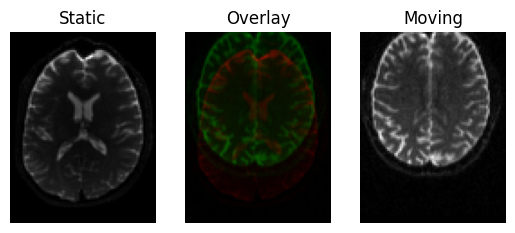

We can see that the images are far from aligned by drawing one on top of the other. The images don’t even have the same number of voxels, so in order to draw one on top of the other we need to resample the moving image on a grid of the same dimensions as the static image, we can do this by “transforming” the moving image using an identity transform

Input images before alignment.